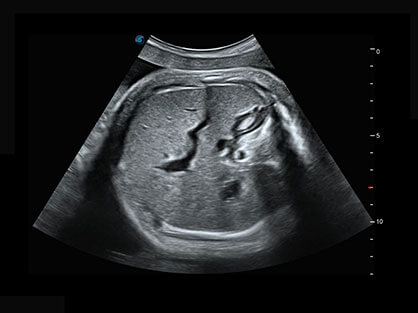

0.5mm厚度的薄层切片显像,可清晰显示微小病灶的连续断面。

可同时显示组织结构表面和内部的轮廓信息,达到透视效果,为临床提供更丰富的诊断信息。

自动获取标准切面,自动完成测量,帮助医生快速完成检查,同时提升测量准确性。